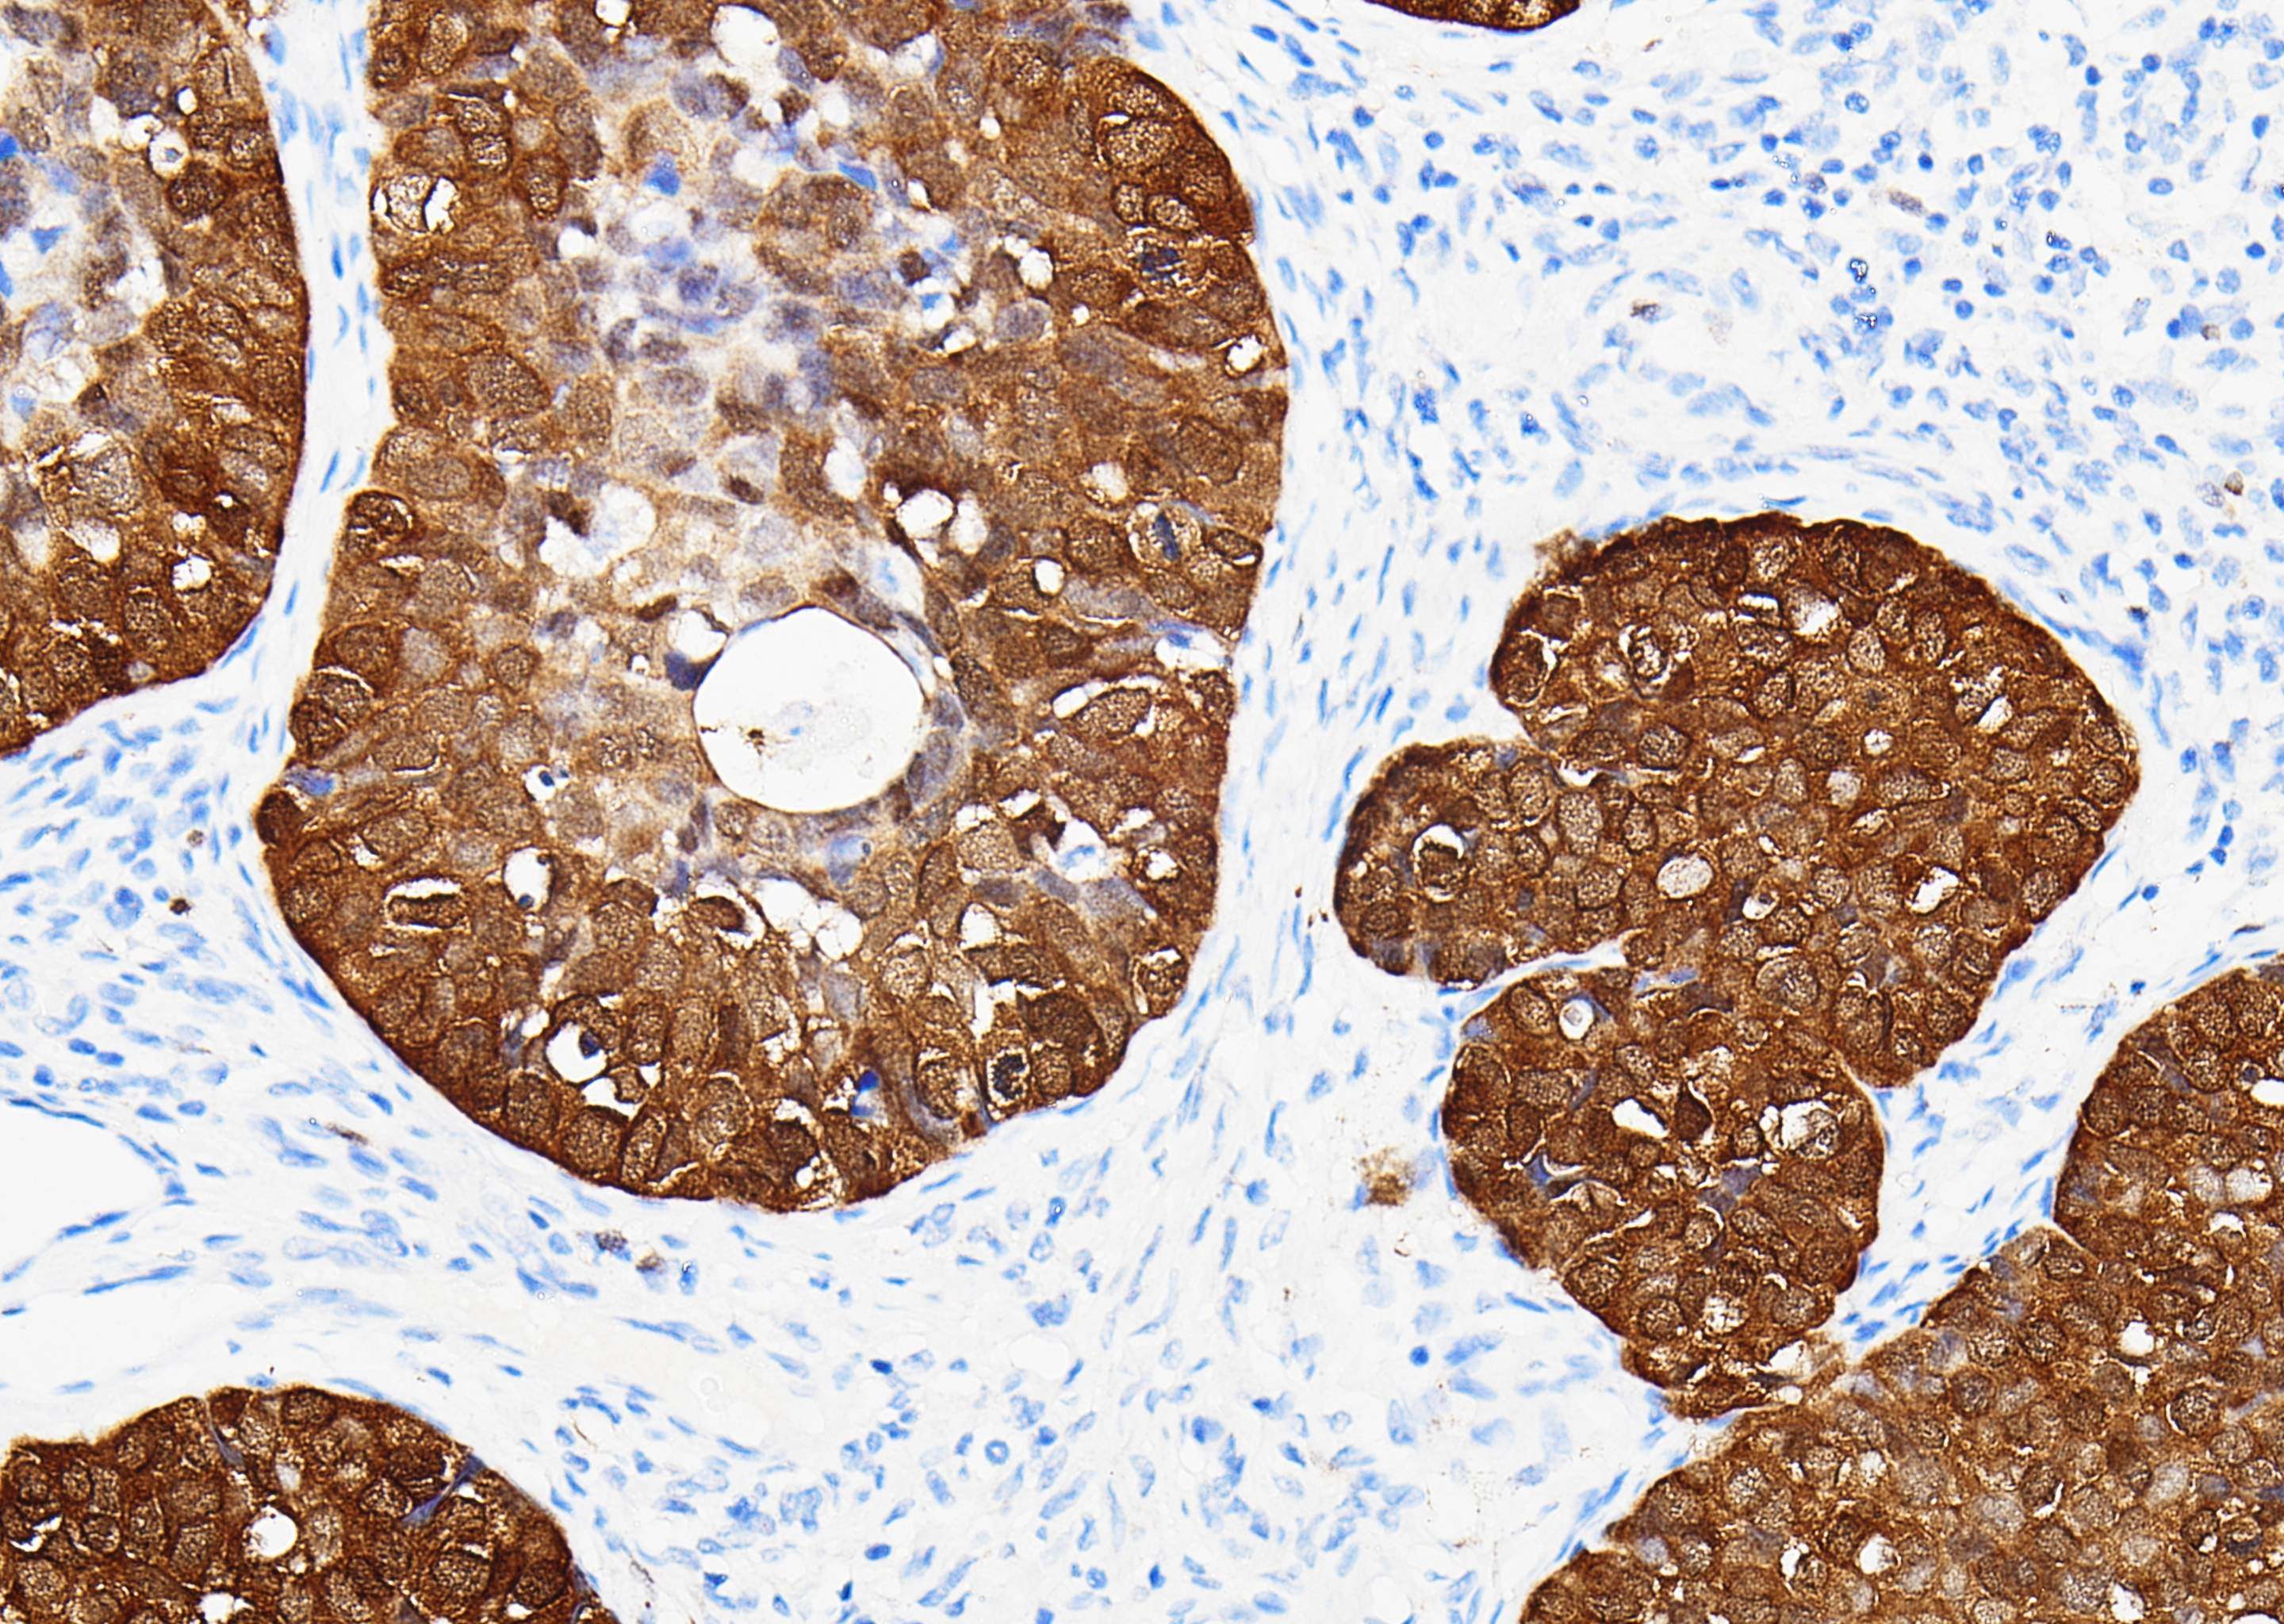

Caldesmon

Caldesmon (钙调蛋白结合蛋白)是一种平滑肌肌动蛋白和钙调节蛋白的结合蛋白,位于细肌丝,调节 肌动蛋白和肌球蛋白的相互作用,主要存在于平滑肌细胞。Caldesmon 可用于正常平滑肌细胞及其肿瘤的标记,真性平滑肌肿瘤与肌纤维母细胞瘤、卵巢/腹膜浆液性乳头状癌与上皮样间皮瘤的鉴别,与CD10 联用 可用于子宫内膜间质肉瘤与子宫平滑肌肿瘤的鉴别诊断。